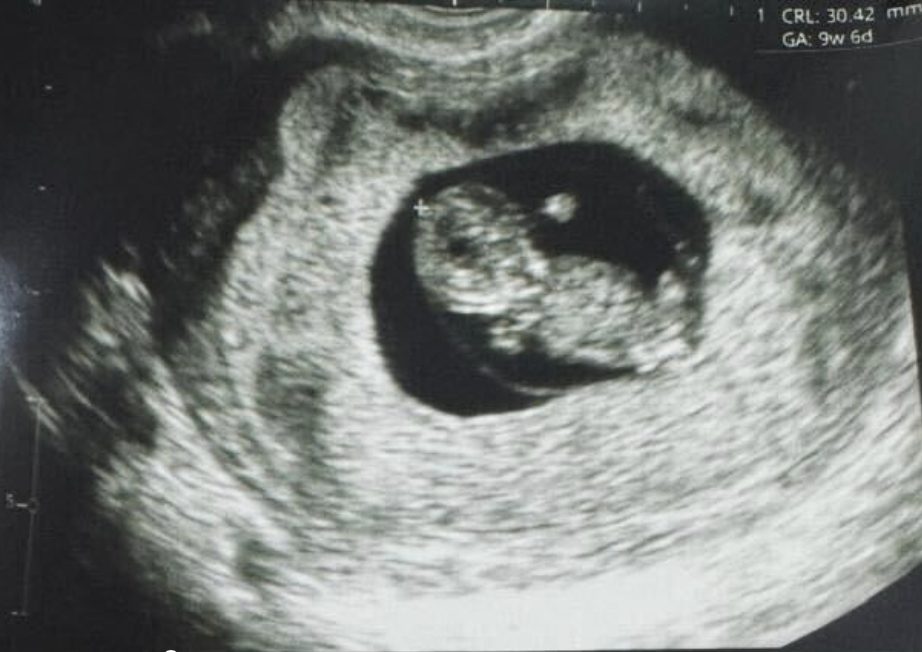

嬰兒的放射線(xiàn)圖像